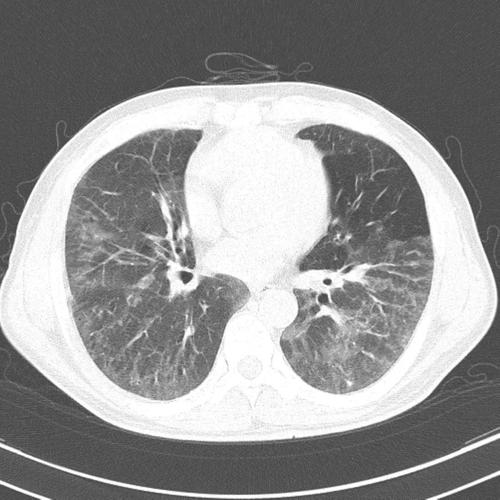

间质性肺炎影像学,间质性肺炎肺纤维化

网格 ≈ 间质性肺炎 间质性肺炎的影像学表现,复杂的很复杂,有时候和

间质性肺炎ct

间质性肺炎ct表现

间质性肺炎ct图片

间质性肺炎早期ct图片

间质性肺炎ct图片特点